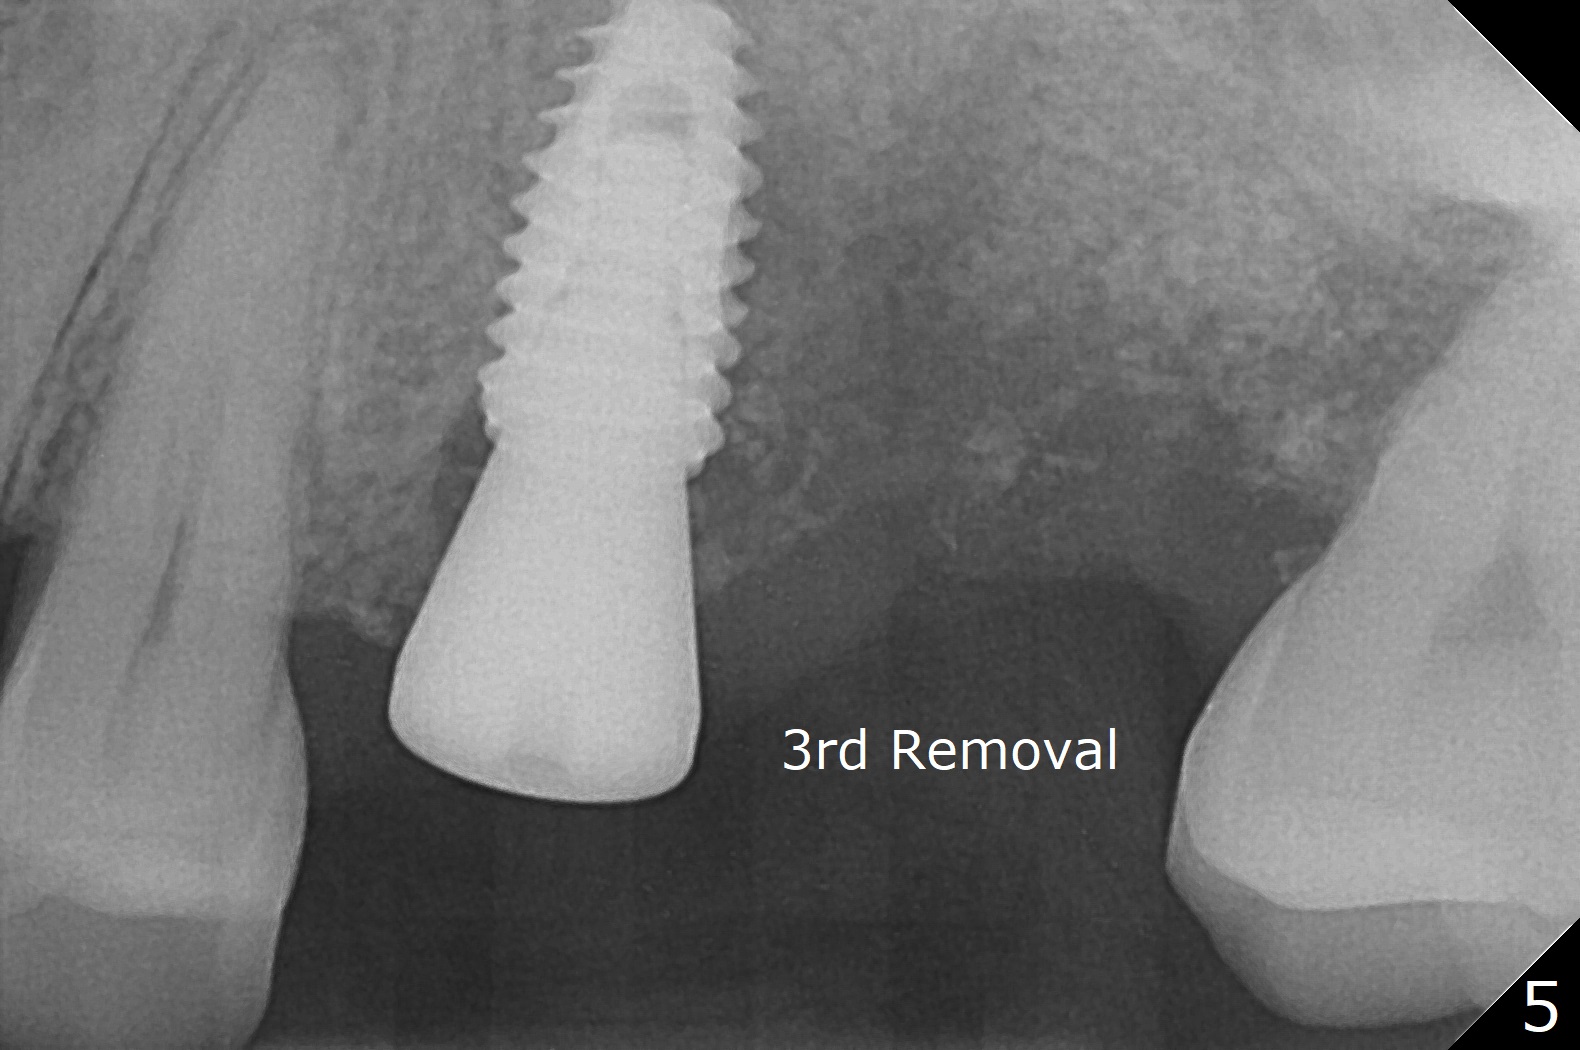

Fixture mount does not fit at #13 as an anchor. After 3.5x7.3 mm drill with 10.5 mm offset at #14, sinus lift drills (3.6x18 and 19 mm) are used. The sinus floor is intact. A 9 mm offset should be used. Following 4.0x10 mm dummy implant is placed for ~ 8.5 mm, the sinus floor is perforated while the sinus membrane is intact. After water lift, PRF membrane and allograft are inserted and pushed upward with the 4.0x10 mm dummy implant for ~ 10 mm (Fig.1). One more piece of PRF membrane and bone graft are lifted with a 4.5x10 mm dummy implant. A small dose of bone graft is elevated with a definitive implant (Fig.2,3, 5x10 mm). Is there enough bone to cover the apical part of the implant when the latter heals? When the patient returns for restoration 4.5 months postop, local oral hygiene is not good with light gingival erythema. There is tenderness when the healing abutment is being removed. It appears that osteointegraton is to occur; the mesial bone density is low (Fig.4 *). Healing abutment should be not placed when sinus lift repeatedly fails. In fact the implant is removed with the healing abutment 6.5 months postop. The buccal plate is missing, while the sinus floor is intact. Ossogen is placed, covered by Osteogen plug and sutured with PGA (Fig.5). The buccal plate remains concave 8 days postop (Fig.6 B). In the 4th trial, incision will be made, flaps dissected extensively with suture fixation. The existing guide is used to start osteotomy with point drill, followed by bone expansion. Reload the guide to place a narrower implant 4 or 4.5 mm with cover screw, and place sticky bone buccal. The latter is covered with PRF and suture. If stability is insufficient, perforate the sinus floor. Place a cemented abutment at #13 to hold periodontal dressing. Use profile drill if needed.Return to Upper Molar Immediate Implant, Trajectory II Xin Wei, DDS, PhD, MS 1st edition 08/13/2019, last revision 02/13/2021